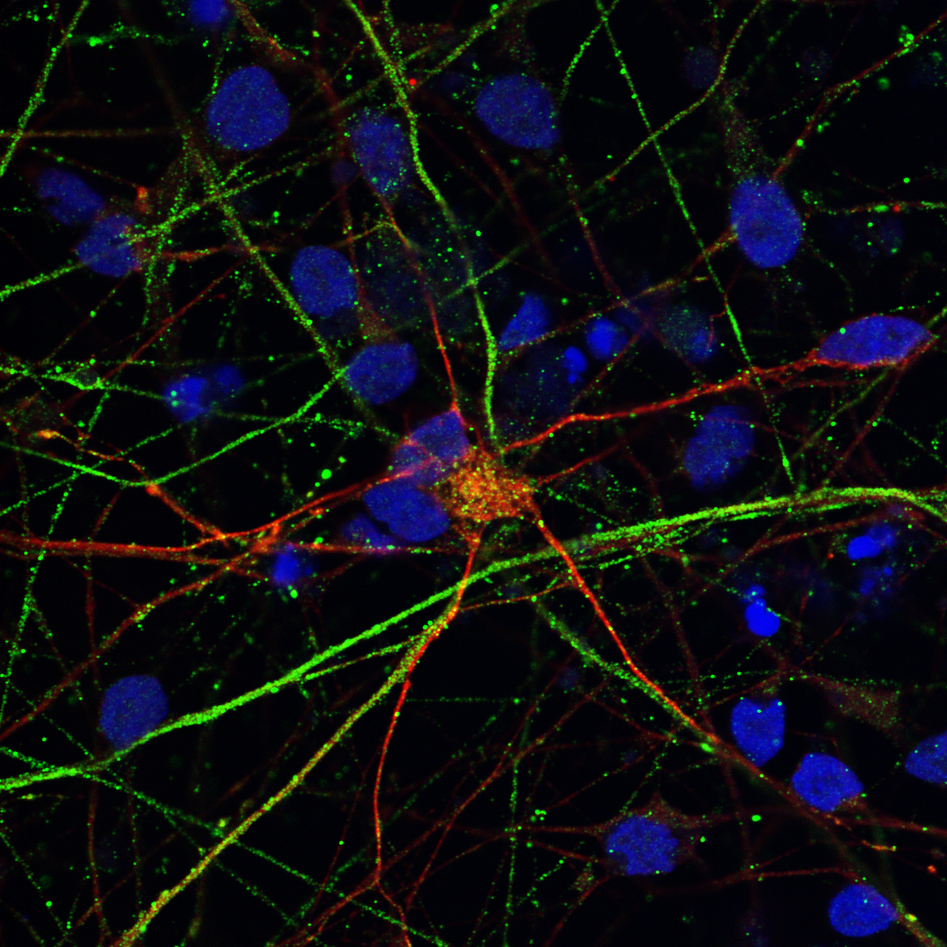

We have established the required competence and facilities for human induced pluripotent stem cell (hiPSC) reprogramming and differentiation, enabling investigation of neuronal cells from patients and healthy controls. Validated iPSCs are differentiated to neural stem cells (NSCs) and regionalized neuronal subtypes, as well as astrocytes/ glial populations. A postdoctoral fellow in our group, Yu Hong, has developed brain organoids and will be using these both to investigate disease mechanisms and to test treatments.

- 2D: neural stem cells, DA neurons, motor neurons, generic neurons, astrocytes, oligodendrocytes and cardiomyocytes.

Modeling diseases using neural stem cells, neurons, astrocytes, and astrocyte-neurons interactions.

Investigating metabolic reprogramming between the neurons and glial cells